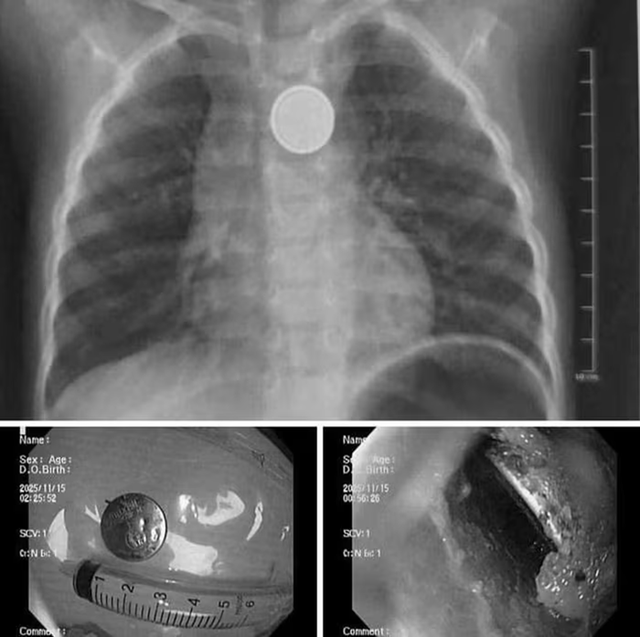

Hình ảnh dị vật là pin cúc áo trong thực quản trẻ.

Tại bệnh viện, các bác sĩ đã tiến hành chụp X-quang, kết quả cho thấy dị vật kẹt tại thực quản.

Ê-kíp nội soi cấp cứu đã nhanh chóng tiến hành gắp thành công viên pin ra ngoài. Dù được cấp cứu sớm song qua quan sát trực tiếp, ê-kíp nội soi ghi nhận có vùng ăn mòn, gây loét thực quản.